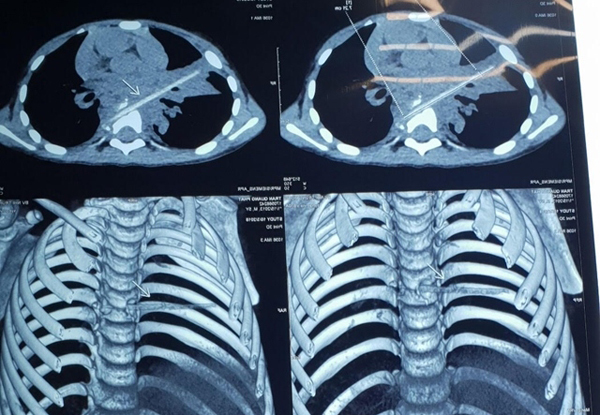

Bé trai bị que xiên thịt đâm xuyên phổi và đốt sống 9 tháng không biết

9 tháng ròng gia đình đưa con trai đi điều trị viêm phổi, tuy nhiên kết quả chụp cắt lớp khiến cả bác sĩ cũng bất ngờ.